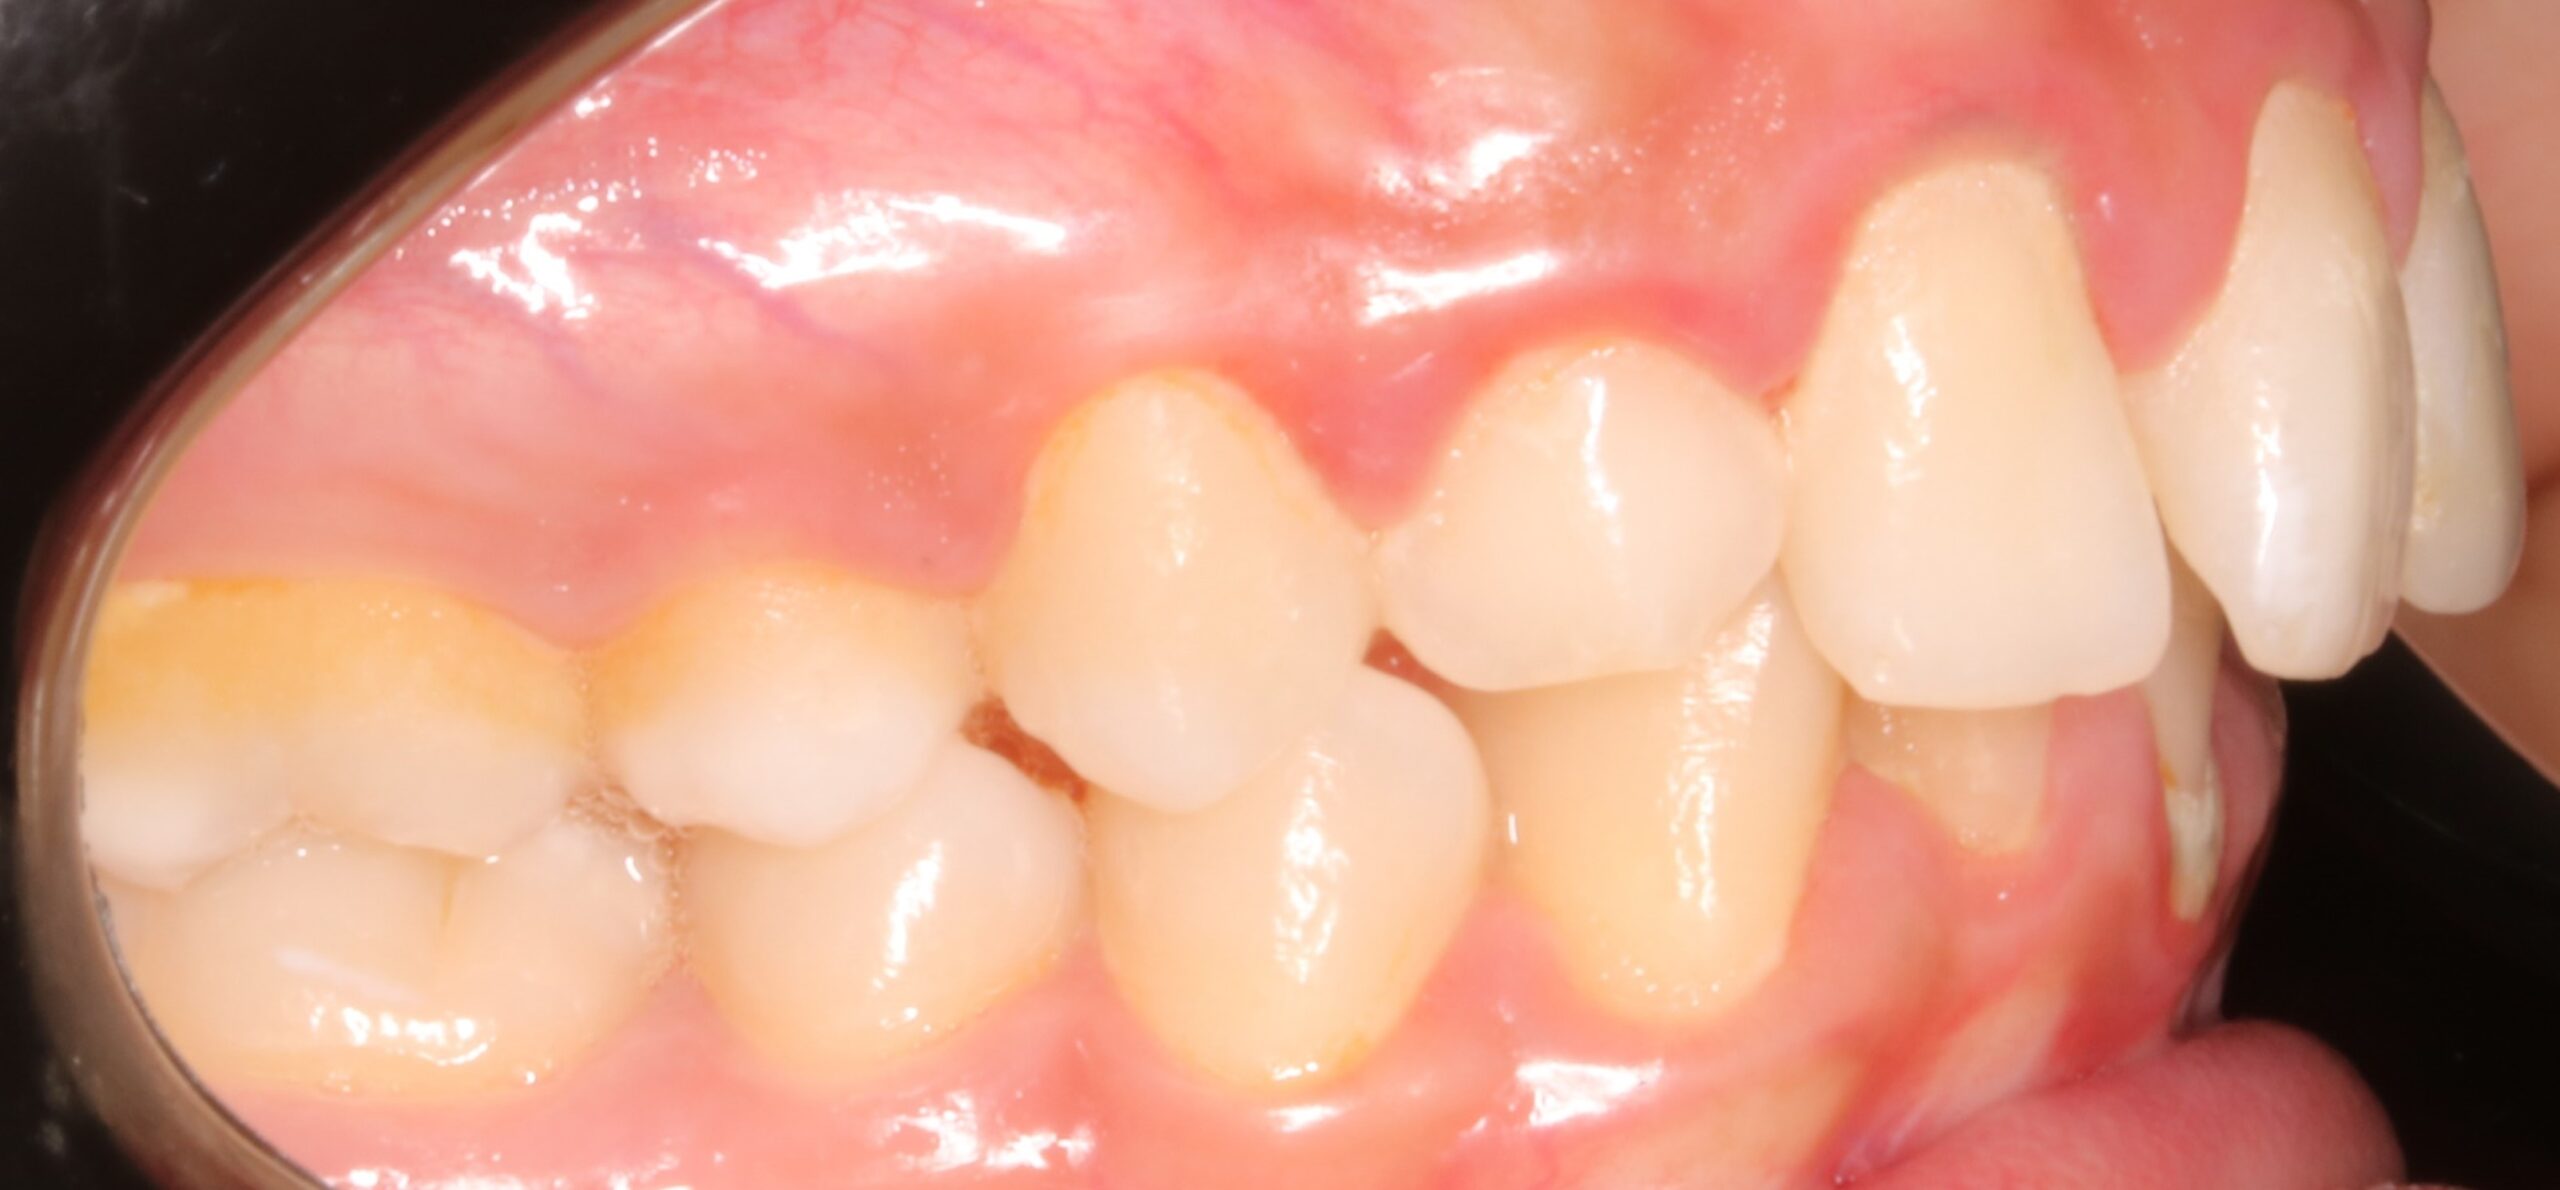

Se muestra el caso de una paciente con un canino incluido en el paladar (pieza 13).

Como principal escollo, nos encontramos con una activa enfermedad periodontal y una deficiente higiene oral. También hay otros problemas secundarios que no hay que desdeñar: apiñamiento inferior con Bolton; leve apiñamiento anterosuperior; malposición de los cordales 48 y 38; rotación del 23; ligera clase II en el lado derecho entre otros. De primera hora se le comunicó a la paciente que antes de empezar el tratamiento de ortodoncia era necesario realizarse de periodoncia, y que después el/la profesional de esta disciplina, nos confirmara que podíamos empezar nuestro trabajo. También, avisamos de la importancia, de que durante el tratamiento, era necesario acudir al periodoncista cada 2 meses y mejorar la higiene oral.

El objetivo de este caso clínico es explicar el manejo clínico del canino incluido por palatino.